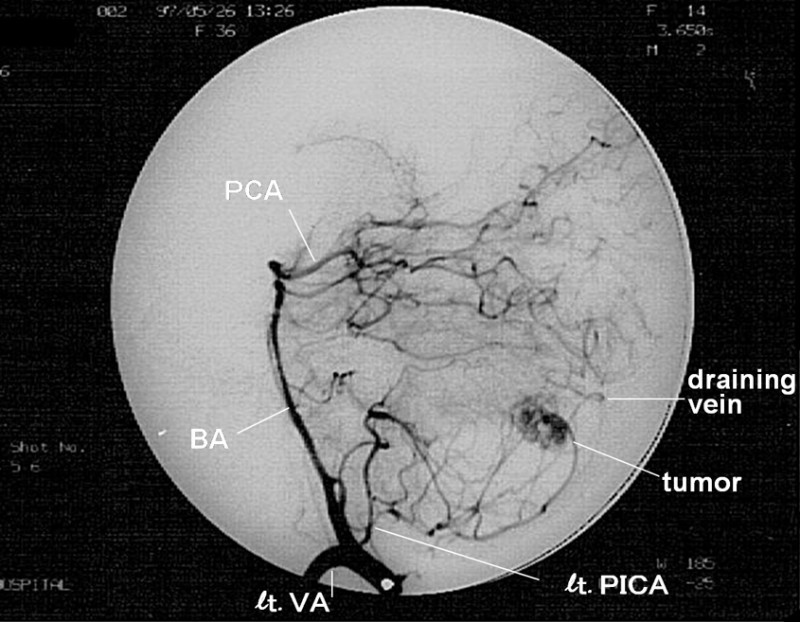

第8病日になされたDAS(digital subtruction angiography)では、左側後下小脳動脈(PICA)の分枝をfeeding arteryとする腫瘍像が抽出され、2本のdraining veinが合流して横静脈洞に注いでいることが判った(図5)。なお、この検査中に本症例は痙攣発作を生じ、そのまま緊急開頭手術となった。

図5 DSAでは、左側PICAをfeeding arteryとする腫瘍像が描出され、draining veinも見出された。

術中所見では、嚢胞を有する壁在結節が認められ、その周囲にfeeding arteryである左側PICA分枝とdraining veinとが見られた。壁在結節を摘出し、手術は終了した。

血管芽腫では、小脳の各動脈から供血される腫瘍陰影が、壁在結節に一致して見られる4)。壁在結節を除去することにより根治されるので、脳血管造影検査にて結節の部位と数とを確認する必要がある4)。今回も、脳神経外科入院後、DSAが行なわれ、腫瘍の詳細が描出された(図5)。なお腫瘍の病理組織診断では、血管芽種の確定診断がなされた。